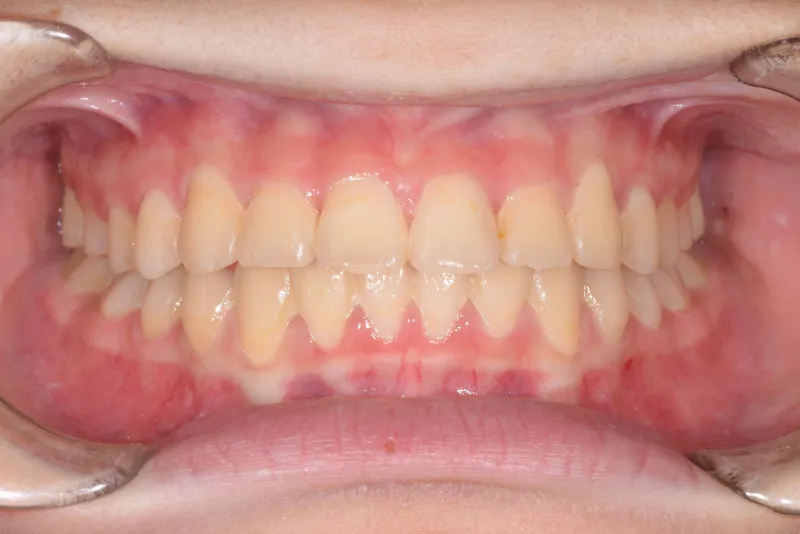

治療終了後

治療回数35回、5年9ヶ月の治療期間で矯正治療を終了しました。